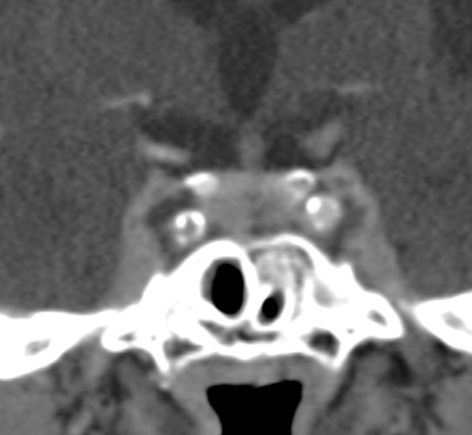

• Complication de sinusite ++

• Céphalées , symptomes occulaires

• Défaut d’opaicifcation

• Tuméfaction avec refoulement du lobe temporal

• Vérifier les veines ophtalmiques

• Vérifier la perméabilité des carotides